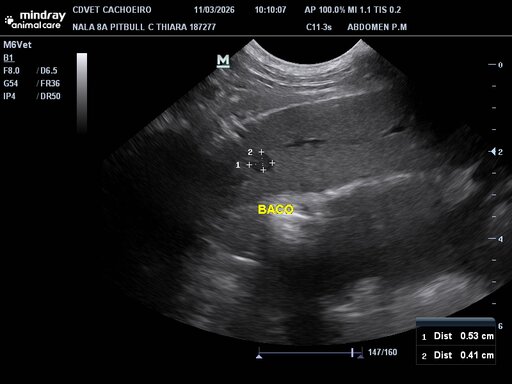

Olá pessoal do bem! Minha cadela Nala precisará passar por uma cirurgia para retirada de uma estrutura nodular no baço e precisaremos da ajuda de todos nesse momento! Desde já agradeço a quem puder e quiser nos ajudar!